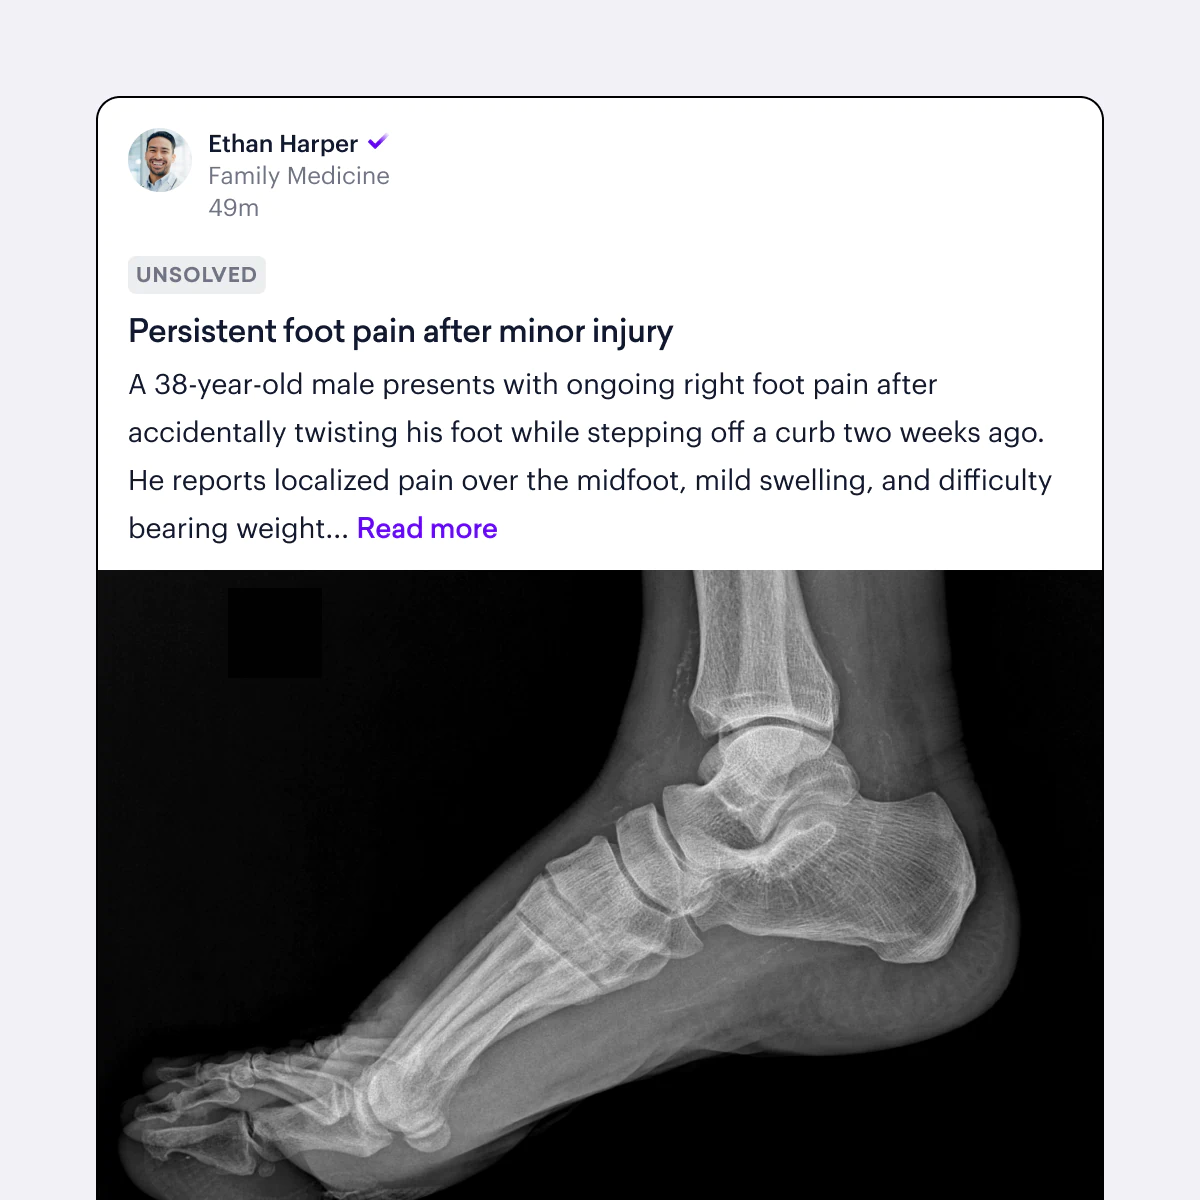

Specialty-specific case studies

Explore case studies relevant to your field, including oncology, cardiology, and emerging infectious diseases. Search, share, and discuss the cases that matter most to your day to day work.